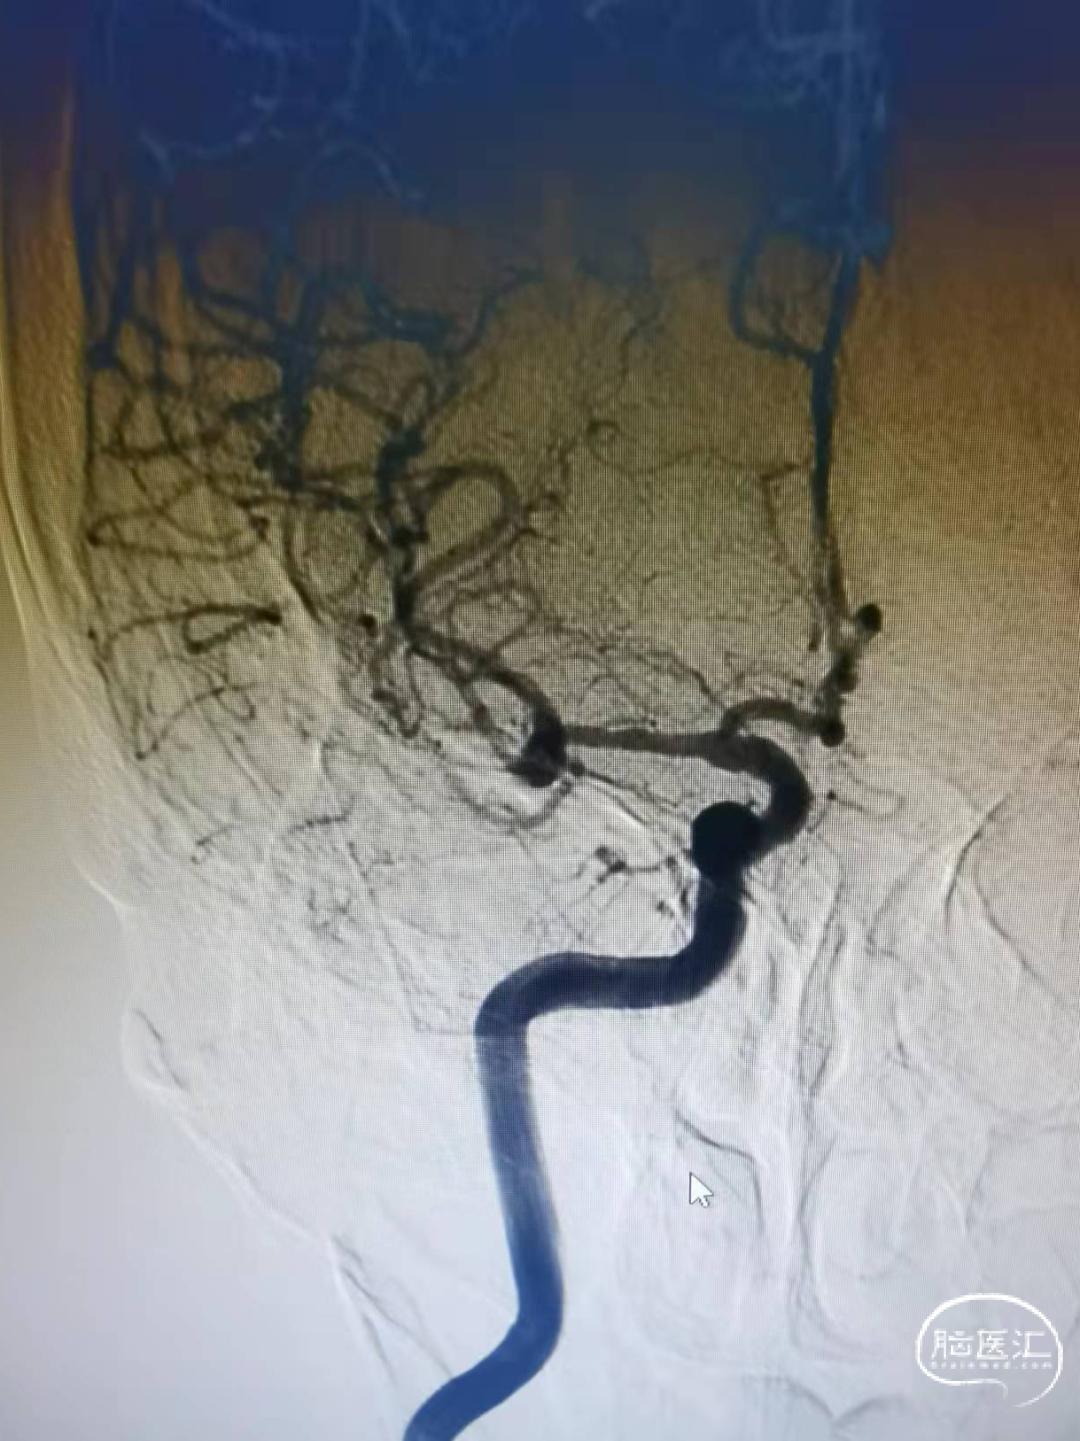

术前影像

头颅CT:左侧内囊后肢腔隙性脑梗死。

头颅MRI:双侧脑室旁异常信号。

头颅MRA:右侧大脑中动脉分叉部结节状突起。

DSA:右侧大脑中动脉分叉部动脉瘤,约3*5mm,颈宽约5mm,伴上下干起始部扩张。

大脑中动脉近端M1直径2.82mm,远端1.83mm,上干1.85mm,下干1.7mm。

术后造影

治疗后正位减影造影,动脉瘤基本致密栓塞,患者术后无明显不适,术后阿司匹林,波立维双抗。目前一般状况良好。(如下动态影像)